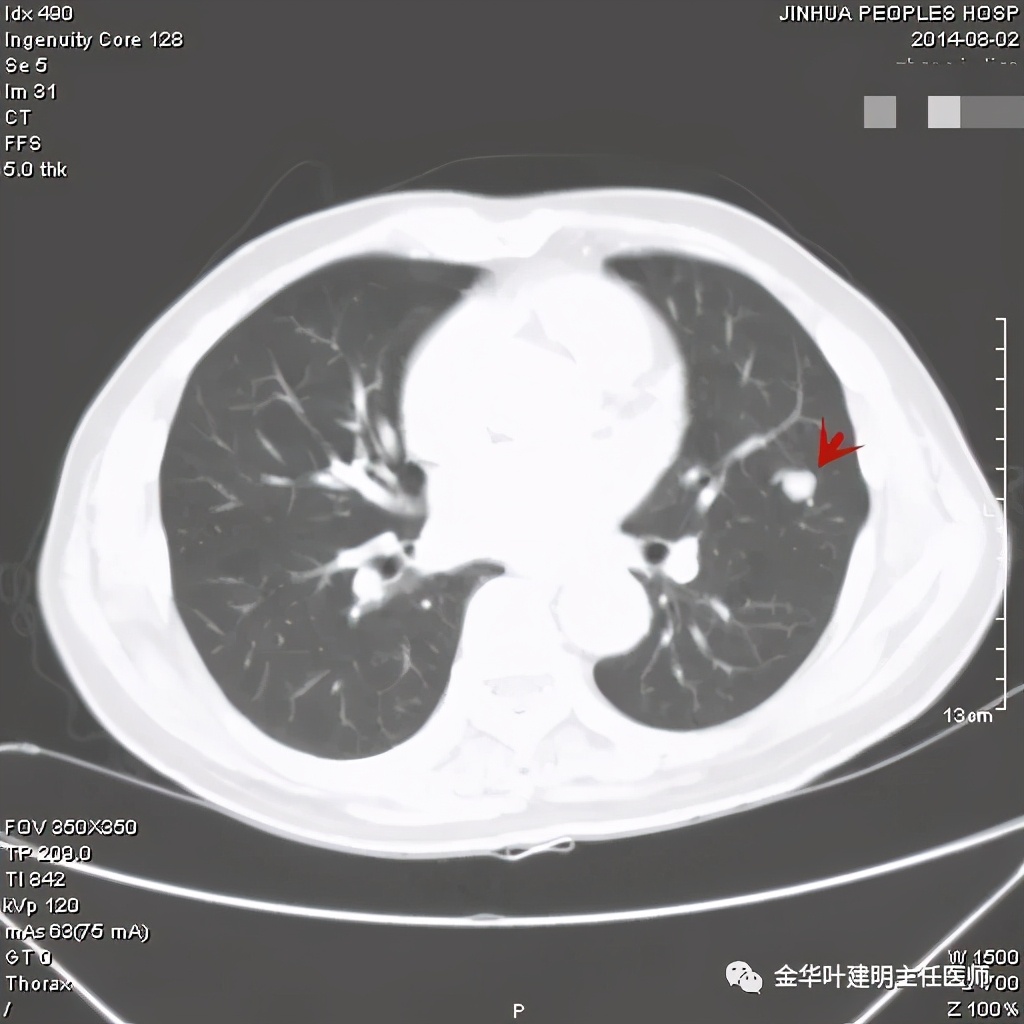

其实今天分享这个病例与我们以往的错构瘤不太一样,以前的影像如下:

亚厘米大小,密度高,周围型,血管贴边

密度高,周围部位,缺乏膨胀性,无收缩力

密度略不均,但边界甚清,边光峭

周围,边缘非常清,病灶内部有点状高密度,约1厘米许,似有微血管征

密度非常高的结节,边缘非常光滑

周围,边缘非常光滑,缺乏收缩力

高密度,周围,边缘非常光滑,亚厘米

高密度,边缘非常光滑,周围

这个也比较大,但边缘非常光滑,密度相对较为均匀

其实我们发现,包括今天这例,只要是错构瘤,“边缘非常光滑”是每一像都具备的!虽然有的似有支气管截断、有的似有血管征、有的似有分叶,但总的只要是边缘非常光滑的实性占位,就要想到错构瘤的可能,若有点状钙化密度,更是强烈要考虑。错构瘤如何靠近胸膜,其实可以切开一点肺实质,挤一下,肿瘤就会滚出来。